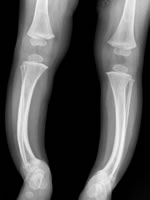

Here again x rays help to demonstrate this clearly. The whiter the image the more the x rays are blocked so the denser the bone. the first x ray on the left is of a normal set of legs.

This x ray shows the legs of a person suffering from Rickets. As you can see the image is much more faded and the bone walls are much thinner. as a result this person is more likely to break bones whereas a normal person might just bruise themselves.